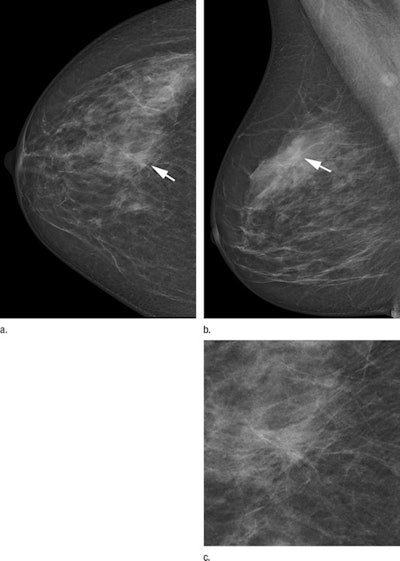

Two-view screening mammograms obtained with the DR photon-counting system show a spiculated mass in the right upper quadrants (arrow). The diagnosis was invasive ductal carcinoma, 8 mm in diameter, as seen on the (a) right craniocaudal image, (b) right mediolateral oblique image, and (c) zoomed in craniocaudal image of the lesion. Images courtesy of RSNA.Exceeding guidelines